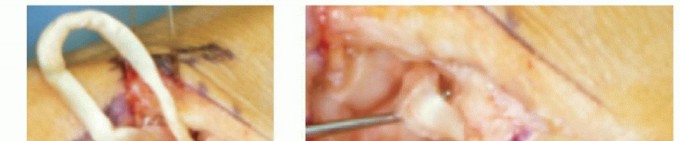

1. Incision and Superficial Dissection

We begin with a triradiate or Wagner-type incision centered over the anatomic snuffbox and the base of the thumb metacarpal. I prefer the triradiate approach as it provides expansive exposure of the dorsal capsule and facilitates proximal visualization of the STT joint. If a concomitant first dorsal compartment release (De Quervain's release) is anticipated, a slightly more volar longitudinal incision may be preferred.

Image

As the skin is incised, extreme vigilance is required. The superficial branches of the radial sensory nerve (RSN) reside immediately deep to the dermis in the subcutaneous fat. Using fine tenotomy scissors and blunt spreading techniques, these branches are meticulously identified, mobilized gently, and retracted. Small vein retractors or vessel loops (applied loosely) can be used to protect the RSN branches, ensuring they are kept out of the working field without inducing traction neuropraxia.

If the patient presents with a prominent "shoulder sign" (fixed dorsal subluxation of the metacarpal base), the distorted anatomy can obscure the true location of the CMC joint. In such instances, palpation of the scaphoid tuberosity proximally and the rigid shaft of the metacarpal distally will help re-orient the surgeon and ensure the incision is accurately centered over the trapezium.

2. Deep Exposure and Radial Artery Mobilization

Deep exposure is achieved by developing the interval between the extensor pollicis longus (EPL) dorsally and the abductor pollicis longus (APL) / extensor pollicis brevis (EPB) volarly. Senn or Ragnell retractors are placed beneath these tendinous structures to open the interval down to the dorsal joint capsule.

Within this interval, the main trunk of the radial artery is identified coursing obliquely over the capsule. The artery is tethered to the capsule by several small, deep perforating vessels. Using micro-bipolar electrocautery, these perforators are meticulously coagulated and divided. This critical step untethers the radial artery, allowing it to be safely swept dorsally and ulnarly using a blunt retractor. Failure to adequately mobilize the radial artery drastically increases the risk of iatrogenic laceration during capsulotomy or trapezial excision.